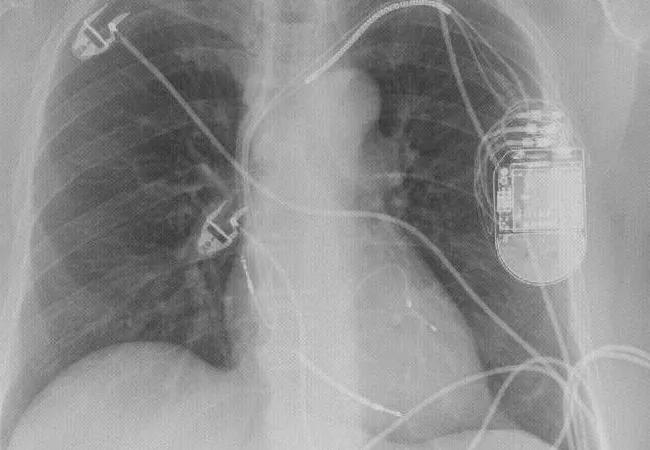

Cardiac resynchronization therapy (CRT) can be a valuable treatment option even in patients with severe left ventricular dysfunction, concludes a new retrospective study published online in JACC: Clinical Electrophysiology.